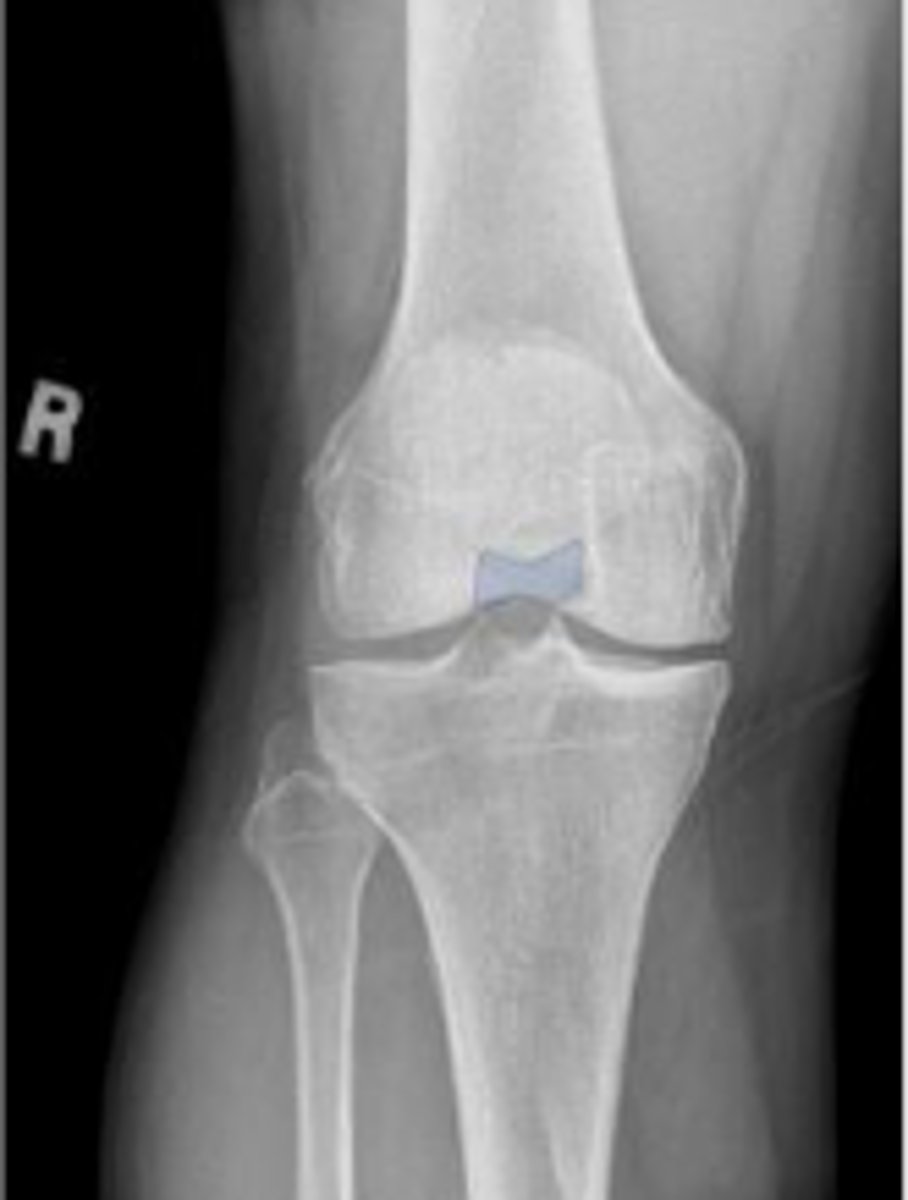

Right internal oblique knee

What is the name of the radiographic view?